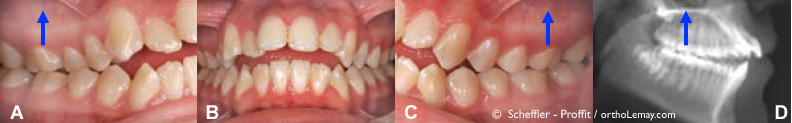

Fig (3) – Importante béance antérieure et constriction maxillaire (mâchoires étroites). Les flèches indiquent le mouvement d’ingression nécessaire sur les dents postérieures pour diminuer la béance antérieure. (D) Radiographie céphalométrique montrant la béance et le contact seulement entre les dents postérieures.

Fig. 1 – Exemples de mini-vis d’ancrage (cercles jaunes) utilisées pour servir d’ancrage à des ressorts qui “intrudent” ou remontent les dents postérieures (flèches bleues) et aident à corriger une béance antérieure. Les ressorts sont aussi attachés sur un appareil intra-oral fixe.